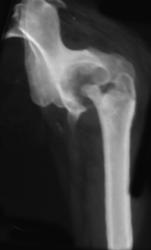

Angiosarcoma